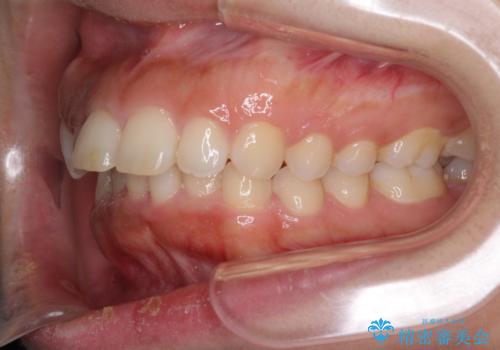

上下顎ともに前突しており、特に上顎は著しい突出感でした。

また、下顎歯列には左右差があり、非対称な抜歯が必要と判断されたため、治療は困難なものとなりました。

それでも根気強く通院してくださり、横からの顔貌の印象が大きく改善され、スムーズに口が閉じられるようになりました。